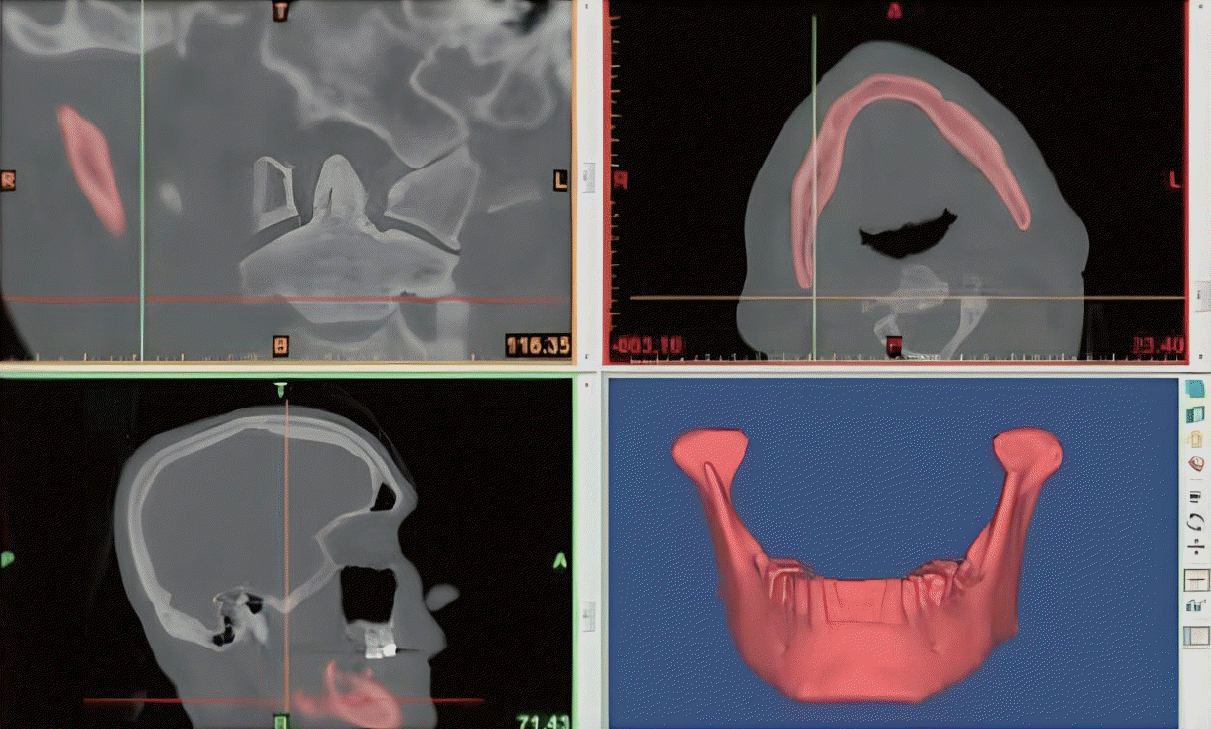

We used the Mimics Innovations Suite software program (Ver.23; Materialise, Leuven, Belgium) for VSP. This technique began with the collecting of high resolution-angiographic CT scan of the patient’s facial bone and lower extremity. The acquired digital imaging and communications in medicine (DICOM) data format from thin-section (1.5 mm) high resolution CT were sent to the 3D modeling company to create a 3D images (Fig. 2). We were able to determine the oncological safe surgical 2 cm-margin of subtotal segmental mandiblectomy using the created 3D reconstruction mandible images before the surgery (Fig. 3A). The next step is the merging of 3D reconstructed mandible and fibula images to determine the design and molding of the fibular bone flap according to the virtual resection of tumor margin (Fig. 3B). We could simulate the fibular bone flap to restore the pre-mandibulectomy shape of the mandible according to the range and location of the defect. And the length and angle of a three-segment fibular bone graft was virtually designed according to defect size (Fig. 3C). Based on these results, we could create 3D models including neo-mandible, mandiblular and fibular cutting guides through sending the VSP data to the modeling company (Fig. 3D-F). Then, the titanium plate was pre-bent according to the 3D neo-mandible models. The 3D models could finally transform the preoperative virtual design into the actual operation device. This process usually took about 7 days. This imaging was used to explain and communicate the patient’s current condition, extent of lesions and purpose and method of surgery. The patients with assistance of VSP have an additional surgical costs.

Preoperative virtual surgical planning. A: Creation of cutting plane of subtotal mandibulectomy. B: Three dimensional (3D) reconstructed mandible with fibula. C: Transformed fibular to anatomic location with cutting planes. D: 3D reconstructed neo-mandible. E: The mandibular cutting guide. F: The fibular cutting guide.